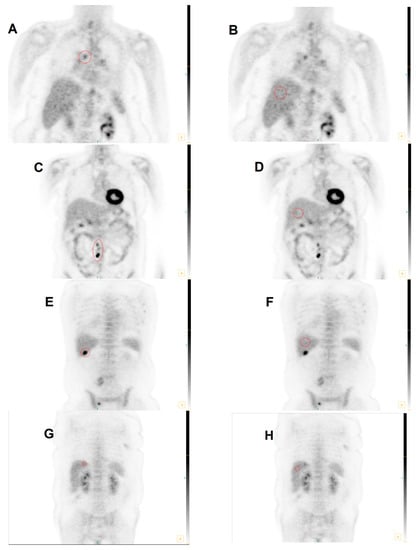

3.2. Group 1: MHLN Lung Cancer Cohort

3.3. Group 2: ETLN Cohort

3.4. Group 3: Hepatic Parenchymal Colorectal Carcinoma Cohort

3.5. Total Cohort